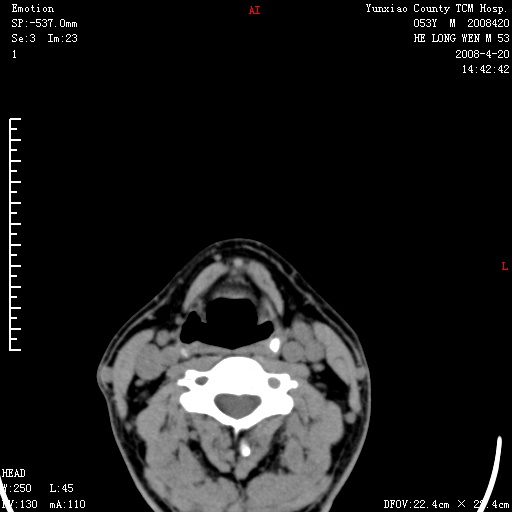

双侧扁桃体肿大:考虑化脓性扁桃体炎。

双侧扁桃体肿大 ,考虑扁桃体炎。

双侧扁桃体肿大,建议结合临床!

双侧扁桃体肿大 ,考虑扁桃体炎

应该有症状,体检此部位不是常规体检项目,支持双侧扁桃体肿大 ,考虑扁桃体炎,但还是强化一下吧。

双侧扁桃体肿大,考虑扁桃体炎,应做一下增强

显示部分为舌扁桃体,腭扁桃体未见显示。会厌显示欠规则,建议喉镜。